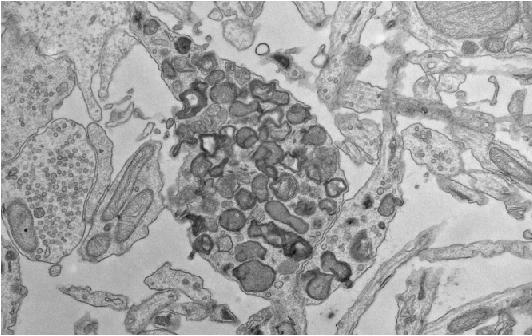

These axonal swellings are packed with lysosomes, cellular garbage disposal units that degrade old or damaged components of the cell. In neurons, lysosomes are thought to "mature" as they are transported from the ends of axons to the neuronal cell body, gradually acquiring the ability to degrade their cargo. The lysosomes that get stuck and accumulate inside the axonal swellings associated with amyloid plaques fail to properly mature, but how these lysosomes contribute to the development of Alzheimer's disease is unclear. One possibility is that they promote the buildup of β-amyloid because some of the enzymes that generate β-amyloid by cleaving a protein called amyloid precursor protein (APP) accumulate in the swellings with the immature lysosomes.

Shawn Ferguson and colleagues at Yale University School of Medicine investigated this possibility by impeding the transport of lysosomes in mouse neurons. The researchers found that neurons lacking a protein called JIP3 failed to transport lysosomes from axons to the cell body, leading to the accumulation of lysosomes in axonal swellings similar to those seen in Alzheimer's disease patients. The swellings also accumulated APP and two enzymes--called BACE1 and presenilin 2--that cleave it to generate β-amyloid. Neurons lacking JIP3 therefore generated increased amounts of β-amyloid.